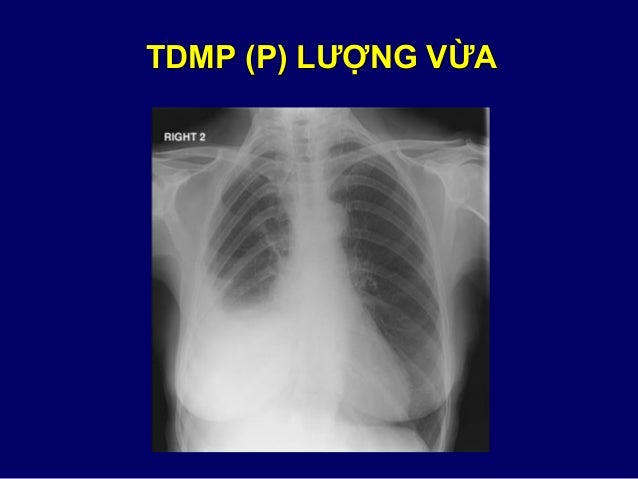

55. 55. HÌNH MỜ / THÂM NHIỄM  Hình mờ: o Vùng nhu mô tăng cản tia XQ và trở nên mờ hơn mô xung quanh. o Không đặc hiệu, không chỉ mức độ bệnh nặng o Cần được gọi tên chính xác là đông đặc, kính mờ, đường mờ .v.v.  Thâm nhiễm: o Trước đây dùng để tả một vùng phổi mờ do bệnh phế nang, mô kẽ o Gây tranh cãi vì mang các ý nghĩa khác nhau o Hiện nay không còn được khuyến cáo sử dụng nữa

56. 56. ĐÔNG ĐẶC / KÍNH MỜ • ĐÔNG ĐẶC: – Đậm độ cao hơn – Bờ mạch máu & phế quản bị xóa – Khí ảnh phế quản (±) • KÍNH MỜ: – Đâm độ thấp hơn – Bờ mạch máu & phế quản không bị xóa

78. 78. 3. TRÀN DỊCH / DÀY MÀNG PHỔI  Dấu hiệu điển hình của TDMP: o Mờ vùng thấp (đáy phổi) o Đường cong lõm góc sườn hoành  Dấu hiệu gợi ý dày màng phổi ≠ TDMP: o Mất đường cong lõm  lên + giảm thể tích phổi o Mờ lên tận đỉnh phổi (cần ≠ TDMP khu trú) o Tổn thương ổn định so phim cũ  Cần phân biệt với xẹp, đông đặc phổi

79. 79. TDMP (P) LƯỢNG VỪA